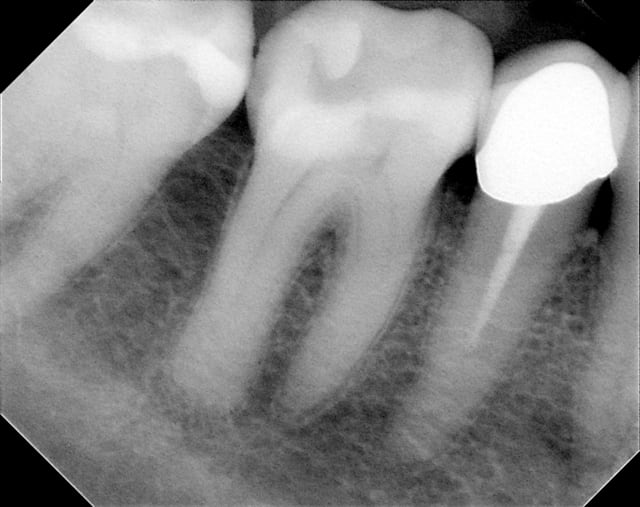

oui, Noah,voici les radiographies de ce patient

j'ai fait un p'tit détour au cab.

merci

flicfac, en ce qui concerne la 46, tu as d'après ton bilan de sondage une atteinte de furcation de grade III, ce qui signifie que ton potentiel de régénération est nul.